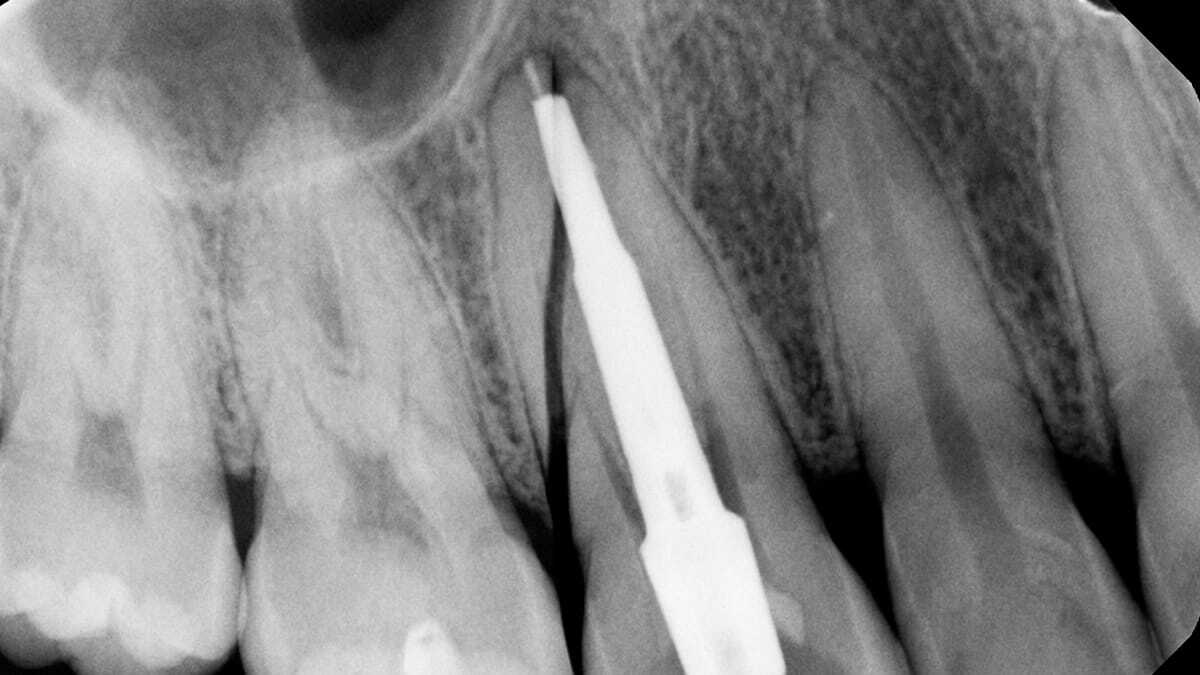

Вертикальный перелом корня

Мужчина, лет 50, пришёл с жалобой на свищ на десне над передним верхним зубом. Зуб под коронкой, на металлическом штифте. Коронку поставили три года назад в другой клинике. Снимаем коронку, делаем прицельный снимок - и там... Вертикальный перелом корня. Чёткая трещина идёт вдоль всего корня, от коронковой части до верхушки. Металлический штифт сработал как клин.

Что характерно: такие переломы часто незаметны первое время. Зуб может не болеть вообще. Инфекция потихоньку просачивается через трещину, образуется хроническое воспаление, свищ. К тому моменту, как пациент приходит с проблемой, спасать уже нечего.

Зуб удалили. Пациент расстроился: "Как же так, совсем недавно коронку ставил, деньги заплатил!" Объяснил, что виноват выбор материала штифта. Если бы три года назад поставили стекловолоконный, с высокой вероятностью зуб бы жил. А так - имплантация, ещё 50 тысяч рублей и полгода лечения.